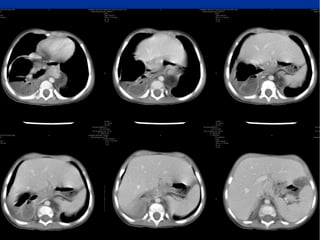

A 7-day-old boy with a

Morgagni hernia. a, b Anteroposterior

(a) and lateral (b) chest

radiographs show a poorly defined

right chest mass and right

upper lung atelectasis. c Sagittal

color Doppler sonogram of the

right chest obtained on the same

day shows herniation of the liver

(L) through an anterior foramen

of Morgagni hernia (arrows).

Note the abnormal course of the

hepatic vein and the difference

in echotexture of the intrathoracic

(T) and intraabdominal (A)

portions of the liver. d, e Sagittal

(d) and coronal (e) contrastenhanced

CT reconstructions

obtained the same day confirm

anterior liver (L) herniation

Hiatus hernia

A 7-day-old boywith a Morgagni hernia. a, b Anteroposterior (a) and lateral (b) chest radiographs show a poorly defined right chest mass and right upper lung atelectasis. c Sagittal color Doppler sonogram of the right chest obtained on the same day shows herniation of the liver (L) through an anterior foramen of Morgagni hernia (arrows). Note the abnormal course of the hepatic vein and the difference in echotexture of the intrathoracic (T) and intraabdominal (A) portions of the liver. d, e Sagittal (d) and coronal (e) contrastenhanced CT reconstructions obtained the same day confirm anterior liver (L) herniation